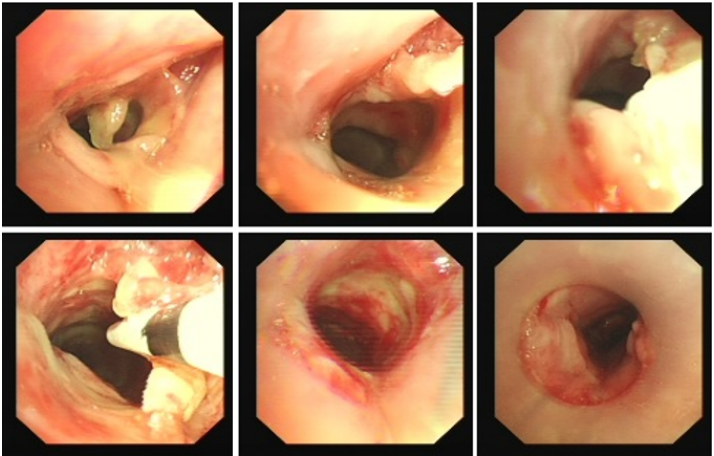

良性中心气道狭窄分为结构性和动力性(6种类型),结构性狭窄包括:管腔内生长(1型),外源性压迫(2型),瘢痕孪缩(3型),扭曲变形(4型);动力性狭窄包括:气道膜部向内膨出(5型),气道软化(6型)。对于动力性狭窄,应考虑用力呼气时的状态,通过操作者的判断,定出最合适、最接近的狭窄程度。治疗方法的制定不仅与气道狭窄程度和长度有关,还与是否存在狭窄过渡段有关。狭窄长度的计算应包括过渡区域。良性气道狭窄形态学分类的诊断方法应通过支气管镜所见及放射学检查来确定。每一个狭窄都可以用4个数字来表示,分别代表部位、类型、狭窄程度、狭窄长度。如:1344代表声门下瘢痕性挛缩性狭窄、狭窄程度>75%、狭窄长度>5 cm,这是一种非常难以处理的良性气道狭窄;2311代表气管瘢痕性蹼状网眼狭窄、狭窄程度<25%、狭窄长度<1 cm,这是一种比较容易处理的良性气道狭窄。热消融技术(APC、电凝、激光)是治疗增生性气道腔内病变(如良性肿瘤和单纯肉芽)的简单、快速的方法。但在治疗瘢痕狭窄病变时,其本身可对气道造成更重、更大范围的损伤,引起更为严重的肉芽组织增生和瘢痕形成,从而导致复发率高,且治疗次数的增加可导致狭窄病变范围增大并最终破坏软骨,导致气道塌陷,使患者彻底失去治愈的机会。电凝和APC仅适合管腔内生长的1型良性中心气道狭窄,并不适合其他类型良性中心气道狭窄的治疗。即便如此,基底部的处理也应避免使用此类治疗方法。针形电刀与气道黏膜接触面极小,不会造成损伤面扩大,瘢痕性气道狭窄的治疗宜选用针形电刀进行切割、松解。因激光也有切割的作用,因此也可选用激光治疗,钬激光、铥激光控制烧灼深度最浅可达0.4 mm,因此更适合良性瘢痕增生性气道狭窄的治疗。冷冻治疗分为冷冻切除(简称冻切,cryoextraction)及冷冻消融(简称冻融,cryoablation)。对于腔内生长的病变可采用冻切治疗,由于容易出血,其安全性不如热消融技术。对于瘢痕病变,冻切技术无法实施,则采用冻融治疗,冻融治疗不促进肉芽组织增生。与热消融相比,冷冻不易导致软骨损伤。通常在热消融治疗接近气道壁时或球囊扩张后采用冻融治疗处理剩余病变,有利于减轻瘢痕再狭窄发生的速度与程度。严重气道狭窄在开通气道前不要使用冻融,因其可引起气道水肿,加重气道狭窄,从而导致窒息。因此,冻融治疗后肺部体征监测及气管镜复查十分重要。机械扩张技术包括球囊扩张和硬质支气管镜扩张,并发症有气道撕裂、再狭窄、出血。(1)球囊扩张:是治疗瘢痕性气道狭窄最主要的技术,其优势是患者治疗后无明显的狭窄段延长,狭窄复发时再狭窄的程度比热消融治疗后轻得多,有利于维持气道复张的疗效。对气管黏膜损伤小,可以在软镜下应用,但需要中断通气。对于挛缩、韧性较强的瘢痕,可先用针形电刀进行切割以松解瘢痕;避免直接暴力球囊扩张,导致气道膜部的撕裂伤。(2)硬质支气管镜扩张:其优势是扩张时不需要中断通气,安全性更好。针对瘢痕肉芽组织增生导致介入治疗后的气道再狭窄,可采用气道狭窄部位局部应用药物的方法抑制瘢痕肉芽组织增生。介入治疗后气道再狭窄可选择的治疗药物有:糖皮质激素、丝裂霉素C、曲尼斯特、紫杉醇等。通过直接植入放射性物质(最常用铱-192)或经过可弯曲支气管镜近距离照射气道瘢痕肉芽组织,促使成纤维细胞凋亡。气道支架置入首选硅酮支架,禁用金属裸支架。支架治疗应作为良性气道狭窄最后选择的治疗技术,启动气道支架治疗的指征:①应用前述各种治疗方法疗效不佳,不能维持气道通畅;②在确定外科手术前临时放置;③外压性气道狭窄;④气道软化、塌陷且无法或不准备行外科手术治疗。病例1:17岁,女性,骨折术后肺炎插管,拔管后(2月14日)气道明显狭窄(图3)。2月15日评估:HR 113次/min,R 24次/min,静息下SpO2 97%(FiO2 50%),咳嗽及说话后喘鸣,有阵发性血氧下降。会诊后拟行急诊介入治疗。2月15日无痛气管镜示:声门下腔黄色及乳白色膜状坏死物,气管上段大量黄色坏死物并管腔重度阻塞,仅见小孔,以冷冻法清除坏死物后管腔通畅(图4)。术后气促明显改善,无需吸氧。病例2:77岁,女性,呼吸困难2个月,加重3天,于2023年12月2日入院(2023年9月气管插管,插管后20余天后拔管)。入院当天查体:HR 125次/min,R 30次/min,静息下SpO2 96%(高流量FiO2 30%),PaCO2 56 mmHg。患者术前影像如图5所示。12月3日查体:HR 140次/min,R 35次/min,BP 190/90 mmHg,SpO2 68%~75%(FiO2 100%),躁动不安,急查血气分析:PaCO2 89 mmHg。紧急床旁无创通气支持下气管镜:气管上段狭窄80%以上,较多黄白黏稠分泌物在狭窄口随呼吸摆动,予抽吸后SpO2升至98%,见狭窄处直径约3 mm,外径5.2 mm,软镜无法进入,遂置入导丝,10#球囊扩张多次,狭窄部位增宽,外径4 mm气管镜引导6.0号气管导管经口插管成功(图6)。插管后患者HR 98次/min,复查血气分析示PaCO2 41 mmHg,氧合指数300 mmHg以上。12月4日气管镜示:右鼻旁路进镜,缓慢退气管导管至声门,距声门3 cm处狭窄,直径7 mm,予12#球囊扩张1 min,2次,未见出血,扩张后直径约12 mm,地塞米松局部保留,气管导管复位(图7)。12月5日拔除气管导管。12月6日气管镜示:气管上段瘢痕狭窄(管径10~12 mm),少许膜状坏死、未见肉芽,予以清除坏死物,7点、11点冻融,术毕注入地塞米松5 mg(图8)。12月13日气管镜示:气管上段瘢痕狭窄(管径12 mm左右),少许膜状坏死、未见肉芽,予以清除坏死物,7点、11点冻融,术毕注入地塞米松5 mg(图9)。